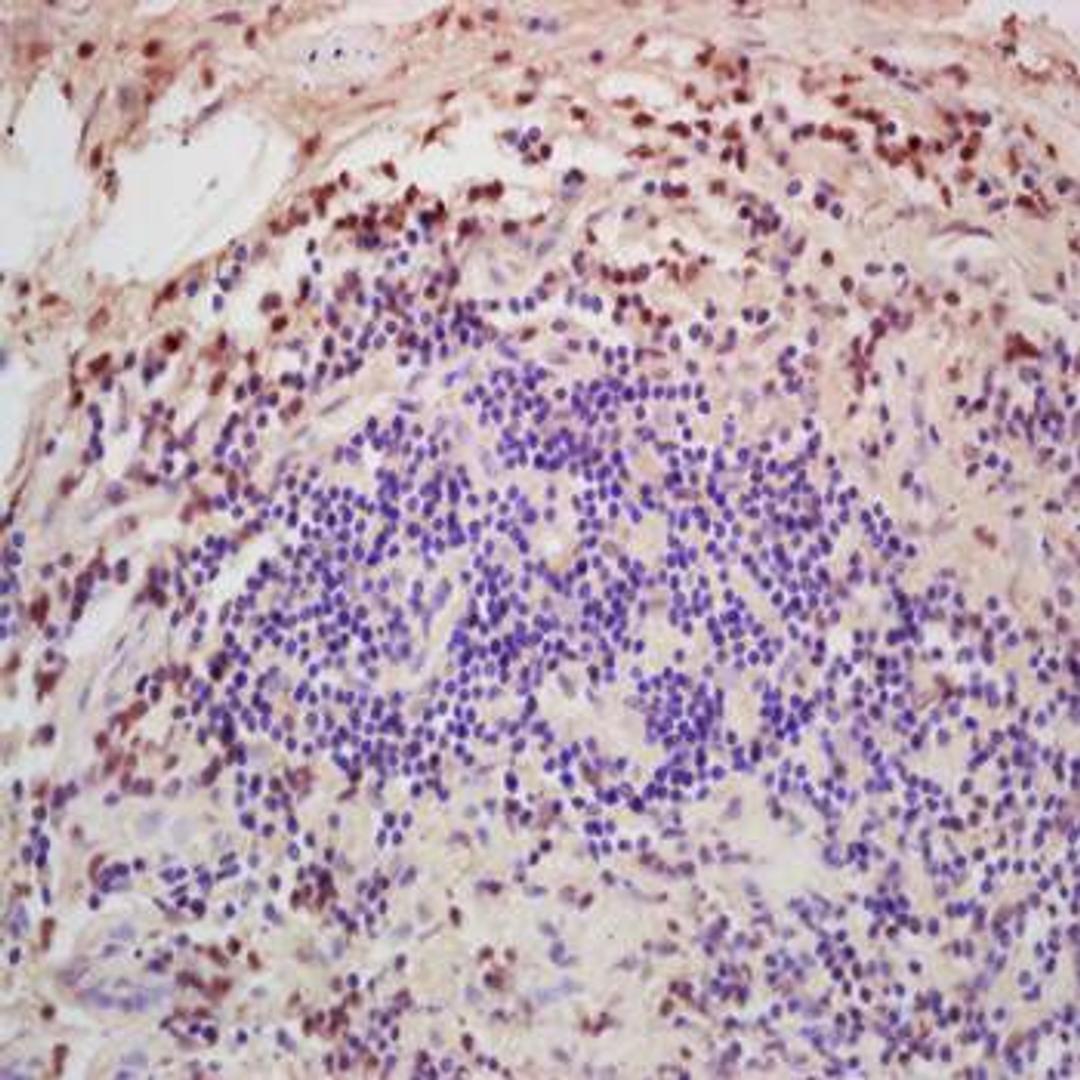

Rabbit polyclonal antibody to CTGFL

- Immunohistochemistry (Paraffin-Embedded Sections) (IHC (P))